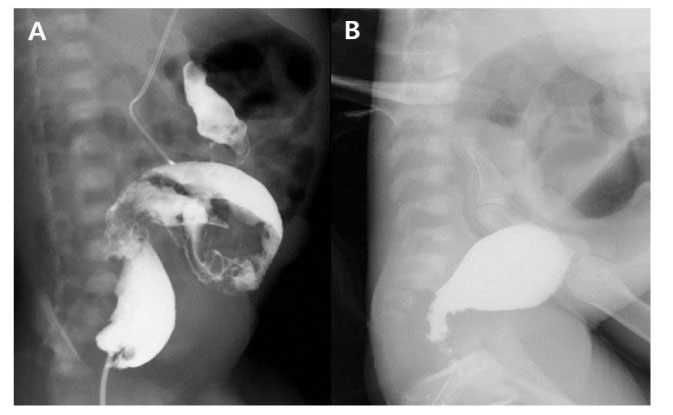

Fig. 1

A case who required repeated contrast enema (CE). Transition zone was not observed in the first CE (A), but clear transition zone was identified in the second CE (B).

Fig. 1 A case who required repeated contrast enema (CE). Transition zone was not observed in the first CE (A), but clear transition zone was identified in the second CE (B).